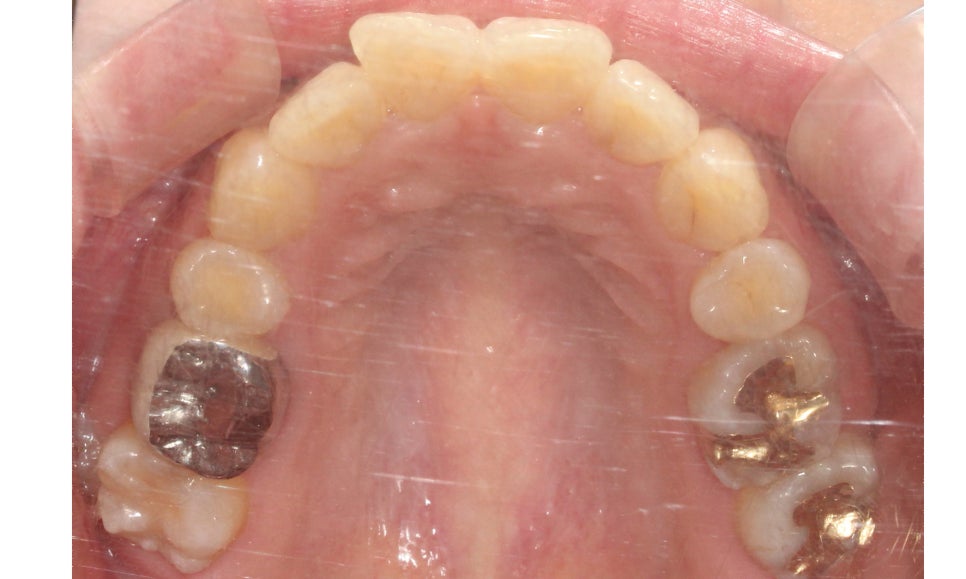

교정 전 상악의 치아배열을 보면

앞니(중절치)부분이 뻐드러져 있고

미세하게 나비치아 성향을 보이는 모습인데요,

마주보듯이 삐뚤어진 상태로

그 모습이 나비의 날개 모습과 비슷하여

이름 붙혀진 증상입니다.